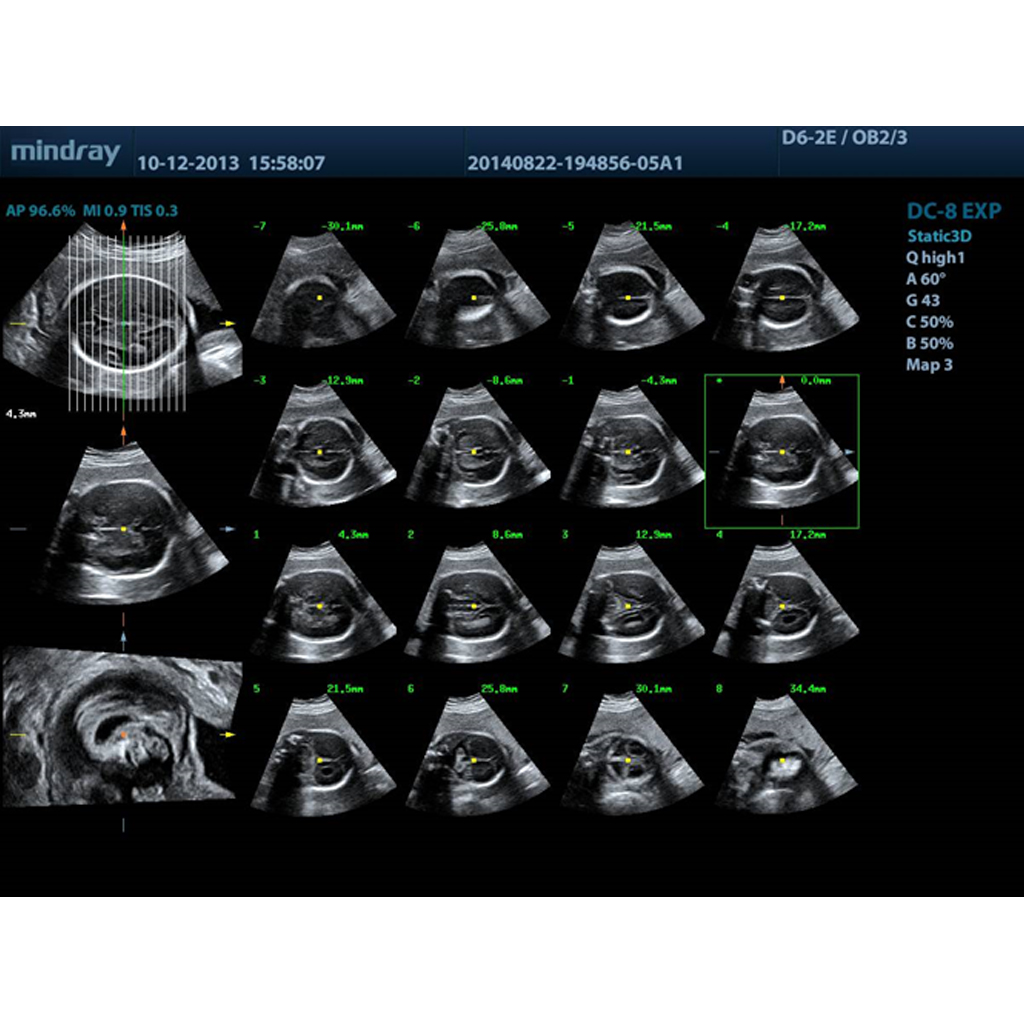

Софтуер за томографско ултразвуково изследване, което дава по-добър и детайлен анализ и диагностика на вътрешни анатомични структури: фетално мозъче и торакс с всички важни структури, анализ на личицето на плода за евентуални малформации

Генерира множество паралелни обемни срезове за детайлно изследване на обемни структури

- избор на желан брой срезове

- избор на различна дебелина на срезовете (от 0,5-5мм)

- избор на ъгъл на срезовете